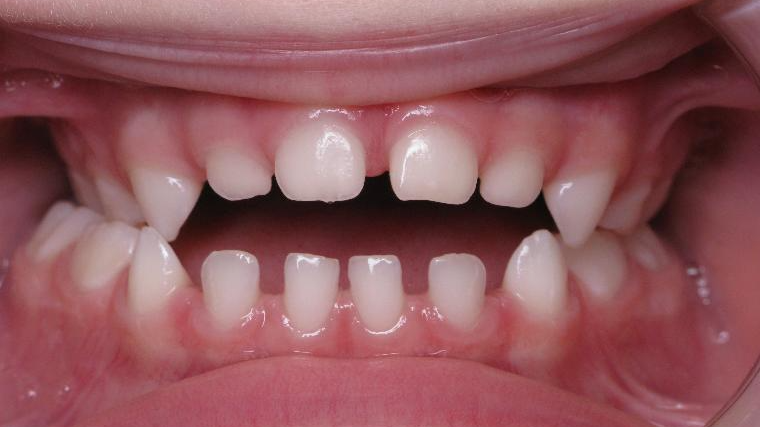

appareillage mobile pendant 35 mois

surveillance évolution de la dentition pendant 5 ans

bilan début et en cours de traitement